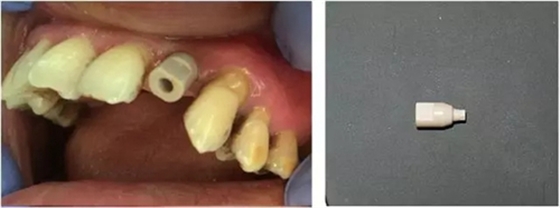

3個(gè)月后,分別使用傳統(tǒng)的轉(zhuǎn)移桿硅橡膠取模以及口內(nèi)掃描取模進(jìn)行修復(fù)(圖5~8)。

圖6 口內(nèi)掃描牙齦袖口

圖7 掃描專用基臺(tái)

圖8 口內(nèi)掃描照片(上頜)